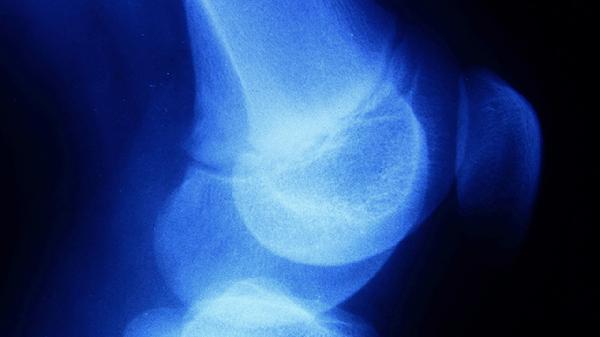

骨骼闭合后长高空间有限,但可通过改善姿势、加强运动、调整饮食、优化睡眠和医学干预等方式最大化剩余潜力。主要方法有姿势矫正、纵向运动、营养补充、生长激素治疗和骨延长手术。

通过伊利扎罗夫外固定架进行胫骨或股骨截骨延长,每年可增长5-8厘米。需承受6-12个月康复期,存在感染、骨不连等风险。仅建议严重矮小症患者选择,需在骨科专科医院完成评估。